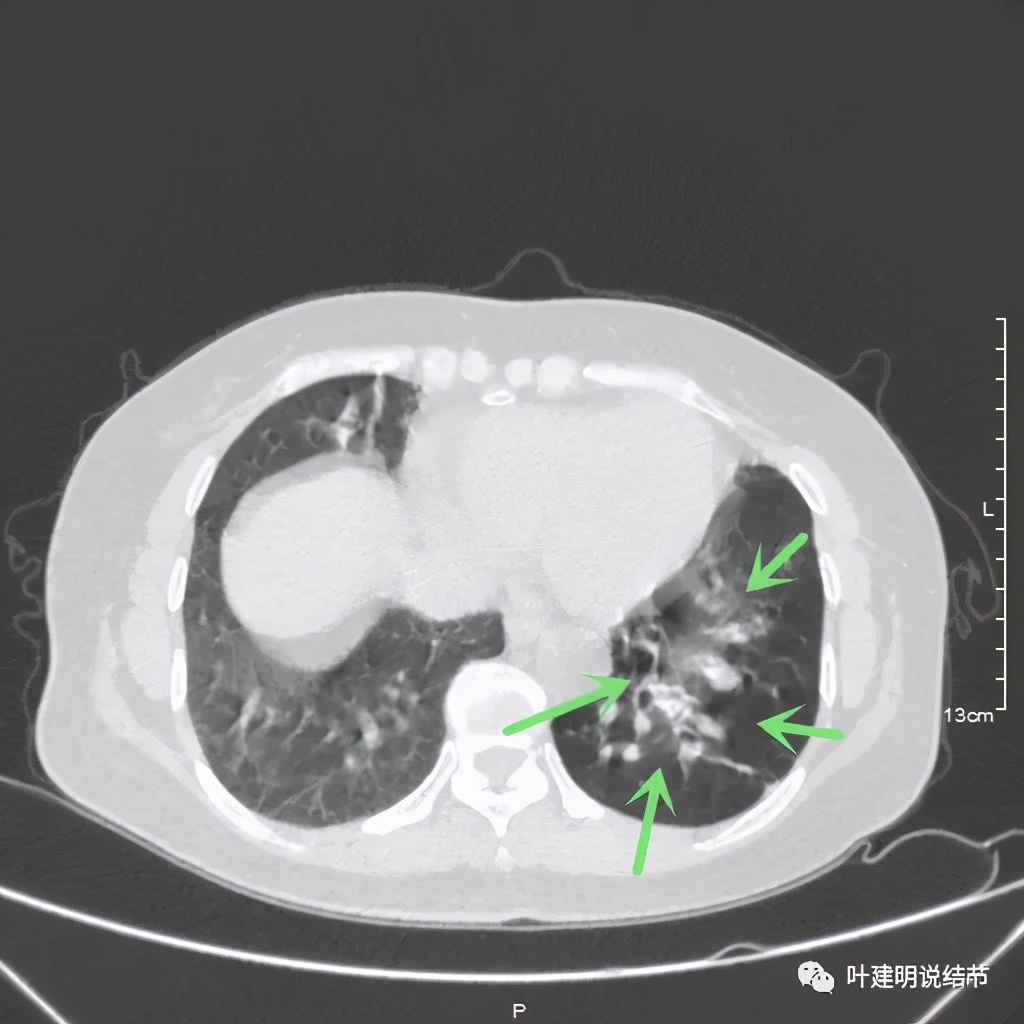

上图见病灶为实性,中间有小空洞,边上有血管进入病灶,靠后侧有棘突样

上图示病灶边缘不光滑,中间有小空洞

上图见病灶边上有血管

上图示病灶血管征较明显,有微小血管从不同方向走向病灶